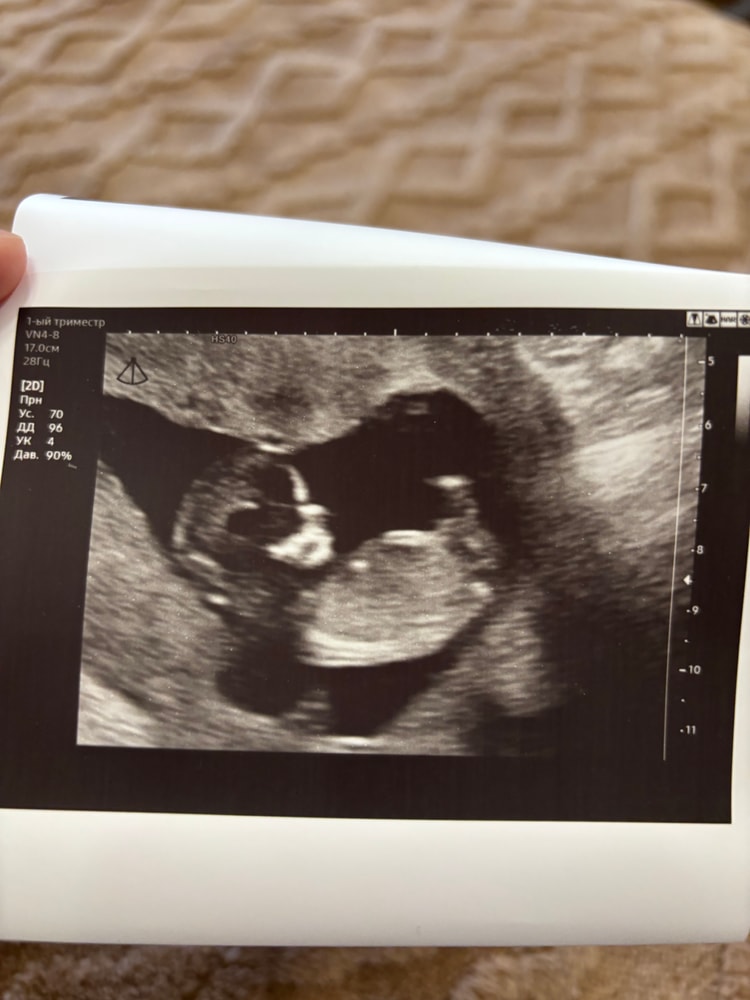

1 скрининг💙

Анализы, скринингиНа днях сходили платно на скрининг вместе с мужем, ибо в жк сказали сразу, что там на скрининг никого, кроме меня не пустят🙈 А мне очень уж хотелось сходить вместе.

По итогу все хорошо, посмотрели все супер внимательно, все рассказали и показали. Малыш сначала спал, лежал тихонько, а потом, видимо, мы его разбудили, начал отплясывать там и рукой махать😁 Пол, кстати, подтвердили сразу, ну, мы и сами все увидели, парень оказался не из скромных😂

Как обычно дали кучу фотографий, послушали сердечко, эмоции остались абсолютно положительные🙌🏻